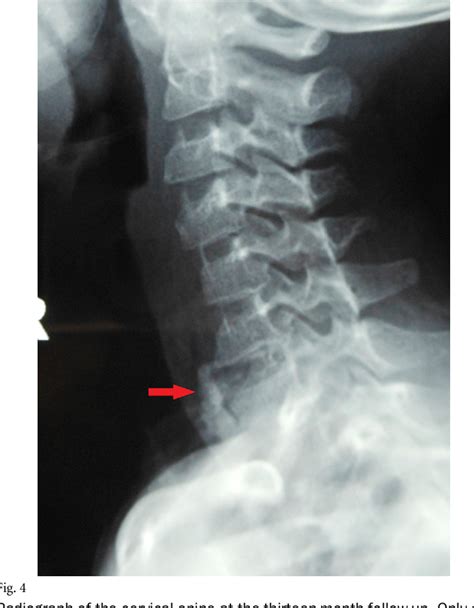

To determine the prevalence, distribution, and location of intervertebral disk calcification (idc) in the thoracic and lumbar spine and the association of idc with. The adjoining vertebral end plates are normal (curved arrows. These findings suggest that osteogenesis in the intervertebral disc is a very slow process first involving the formation of dispersed, amorphous regions of calcification or osteoid. Textbook presentation is child with neck pain, fever, malaise, and an elevated esr. The most common symptom is back or neck pain, but muscle spasm,.